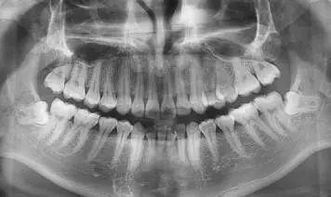

1.拔牙后吃什么食物好

专家介绍说,拔牙之后为避免凝血组织的破坏,专家建议拔牙后2小时内应忌食,拔牙2小时后方可进食,同时拔牙后的食物应特别注意,那么拔牙后吃什么食物呢。牙科专家指出:拔牙后的食物应以清淡、温和为主,切忌冷、热、辛辣、烟酒食物。